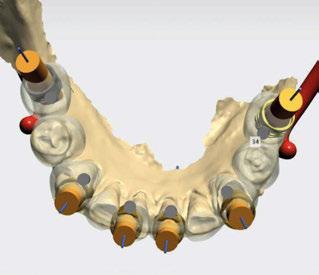

A tenor del estado oral proponemos múltiples opciones terapéuticas, consensuando entre paciente y facultativos una rehabilitación implantoprotésica fija superior e inferior. Debido a la lejanía de la residencia de la paciente, y motivados por las necesidades estéticas que esta exige, consideramos realizar una carga inmediata impresa con resina definitiva el mismo día de la cirugía. Tras el escaneado intraoral con el escáner Dexis IS3700 (Figuras 7 y 8) y realización de CBCT, subimos los ficheros a la plataforma Bego Guide,

procediendo a realizar una solicitud de encargo a través de un formulario. Antes de 72 horas recibimos una propuesta terapéutica. En ella se facilitan vistas 3D detalladas, así como valoraciones y consideraciones a tener en cuenta durante el fresado y la inserción de los implantes (Figuras 9 a 19). Decidimos realizar extracción de todas las piezas remanentes, dada su nula viabilidad a corto-medio plazo y en Bego (a través del portal) proponen mantener 3 piezas (las más viables técnicamente) en cada arcada para proporcionar el anclaje óptimo de la

Figura 9. Propuesta de planificación maxilar con encerado diagnóstico digital. Se visualiza emergencia de los implantes y emergencia protésica con pilares angulados.

Figura 10. Propuesta de planificación maxilar con encerado diagnóstico digital. Destaca la angulación del implante 1.6 esquivando el seno maxilar con un ángulo de inserción de 30 º y una emergencia protésica verticalizada.

Figura 13. Representación gráfica de la futura colocación de los implantes y su relación con la rehabilitación.

16. Superposición radiológica implante 45 angulado, teniendo en consideración el encerado diagnóstico y preservando estructuras nerviosas.

Figura 14. Representación tridimensional. Destaca la protección de estructuras nobles (nervio mentoniano) al presentar un implante angulado con íntima relación.

Figura 15. Visión general tridimensional. Destaca la uniformidad en la disposición de los implantes. En amarillo emergencia implantológica y en gris emergencia protésica mediante pilares transepiteliales angulados multiplus.